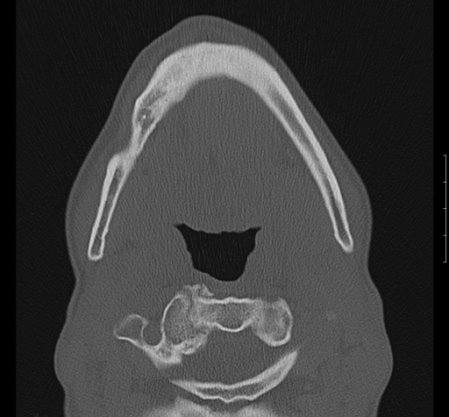

Zur genauen Planung der Kieferkorrektur wurde ich zum CT geschickt. Aus den scheibchenweisen Bildern setzte der Computer ein dreidimensionales Bild zusammen. Dabei ist auch sehr deutlich dieses verlagerte Knochenstück zu sehen.

Zwischenzeitlich stand auch mal die Überlegung im Raum, eine Kinnplastik durchzuführen, bei der die Kinnspitze abgesägt und danach im "richtigen" Winkel wieder aufgesetzt wird. Das klang natürlich auch erst mal ein bissel erschreckend - aber schließlich zählt das Ergebnis. Nach Auswertung der 3-D-Annimation wurde dann allerdings "nur" die erstbeschriebene Kieferkorrektur durchgeführt.